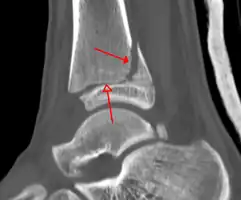

A triplane fracture of the ankle as seen on CT -

A triplane fracture of the ankle as seen on CT